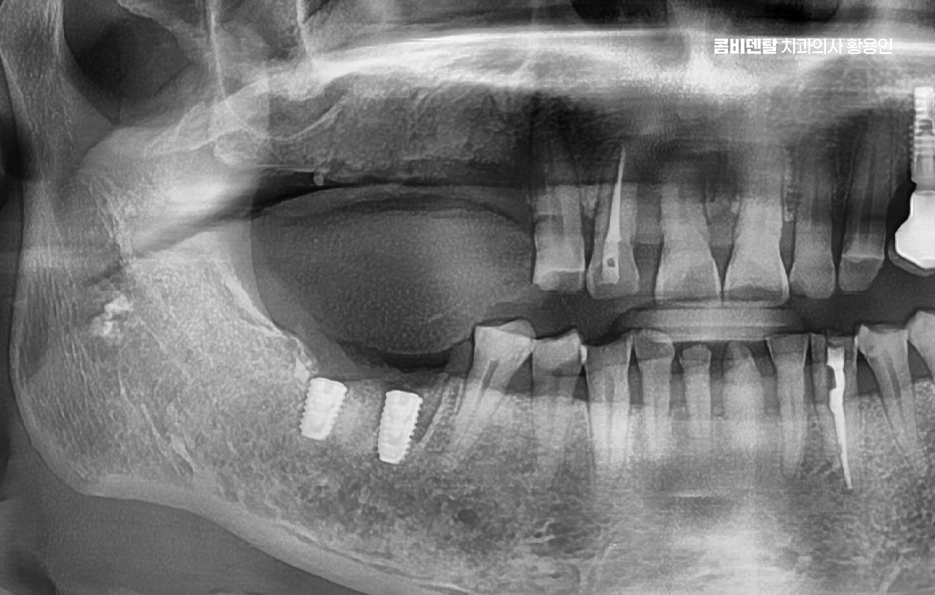

어금니 임플란트 과정은 정밀 진단에서 시작되며 잇몸뼈 안에 인공 치근을 심는 방식이기 때문에 뼈 상태 확인이 필수적으로 파노라마 촬영이나 3차원 CT를 통해 뼈 높이와 폭, 신경 위치를 확인하고 특히 아래 어금니는 하치조신경과 가까워서 정확한 위치 파악이 중요하며 위 어금니는 상악동과의 거리도 고려해야 할 필요가 있어요

임플란트를 심을 잇몸 뼈가 충분하다면 바로 식립이 가능하지만 치아를 빼고 오래 방치한 경우에는 뼈가 흡수되어 부족할 수 있으며 이때는 뼈이식을 먼저 하거나 동시에 진행하고 어금니는 씹는 힘이 강하기 때문에 초기 고정이 단단해야 하며 유지까지 고려할 때 교합의 정교한 맞물림이 중요한 부위라고 할 수 있었어요

어금니 임플란트 과정에서 수술 당일에는 국소마취 후 잇몸을 절개하거나 최소 절개로 접근해 뼈에 임플란트를 식립하며 수술 후에는 일정 기간 골유착을 기다리는데 임플란트와 뼈가 단단히 결합하는 과정이라 할 수 있었어요